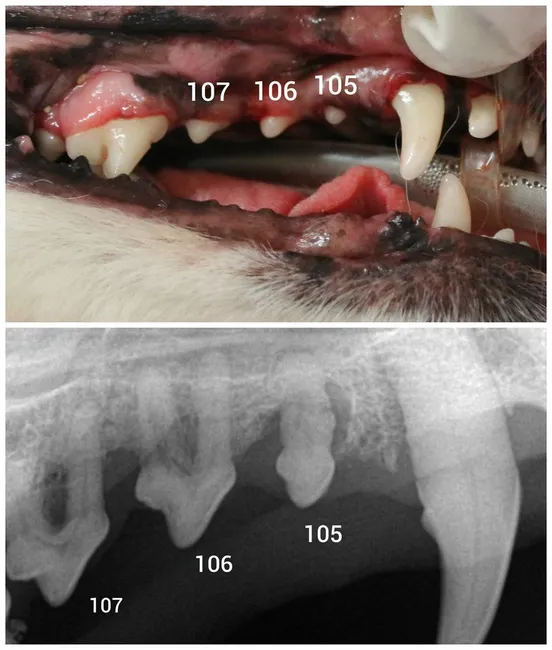

Note in the top picture that the teeth are clean and look healthy.

In the radiograph, the labeled teeth (107, 106, 105) all show significant bone loss and root exposure.

Without dental X-rays, we are essentially making educated guesses about what’s going on below the surface. That’s why we include full-mouth dental radiographs in every dental procedure we perform. It’s the only way to truly diagnose, treat, and protect your pet from hidden disease.